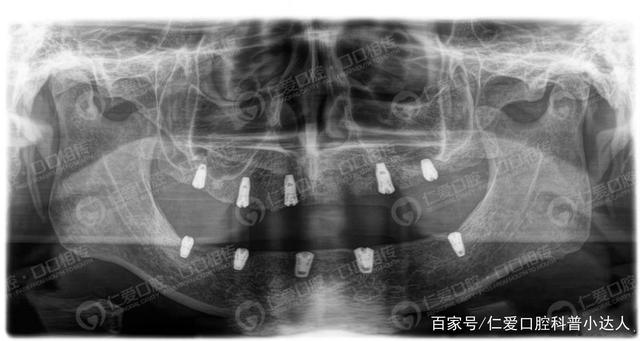

#全口種植牙# 67歲王大爺進(jìn)行全口種植技術(shù)

修復(fù)方案:微創(chuàng)即刻負(fù)重|無切口、無縫合、上下頜各植入6顆種植體,一日即得全口好牙!